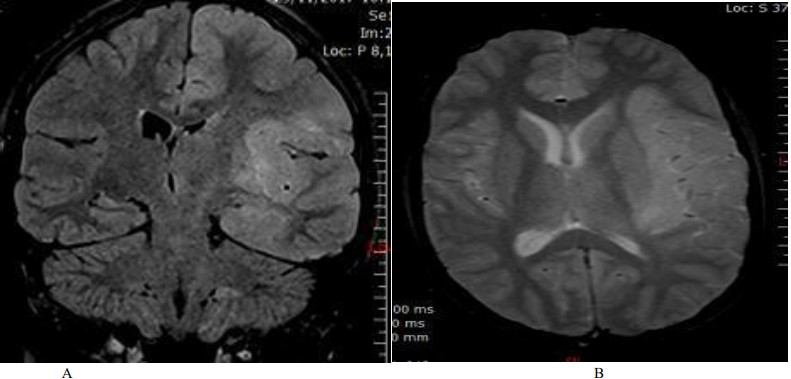

Magnetic resonance imaging (MRI) revealed a hyper signal on the Flair and T2 sequences, without contrast enhancement, unilateral, on the left, touching the fronto-temporo-insular white matter (Fig. 1). The GES highlighted left hemispherical brain pain, without paroxysms (Figure 2). The cytochemical study of the CSF revealed a slight hyperproteinorachia at 0.5 g / l, as well as a lymphocytosis at 30 elements / mm3, and the immunological study did not show a chronic inflammatory process. All serologies were negative (Herpes, HTLV1, syphillis, HIV, Lyme ...), and the autoimunity balance was also negative.

Figure 1. Cerebral MRI: A: coronal section, Flair sequence / B: transverse section, T2 sequence: left fronto-temporo-insular hyper signal.